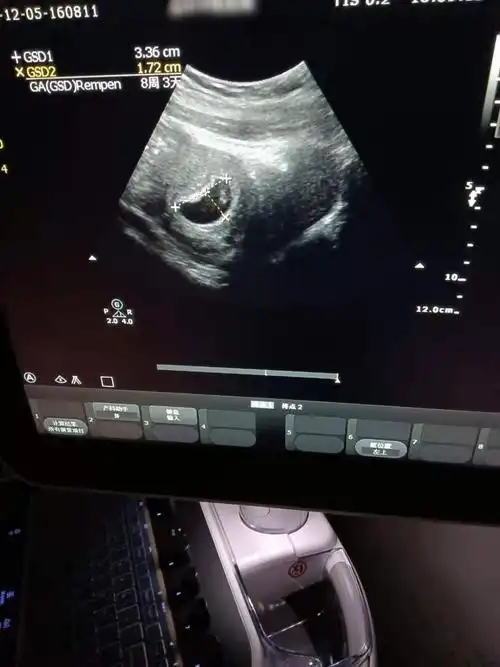

宝宝有胎心胎芽了

接健康胎心胎芽喽